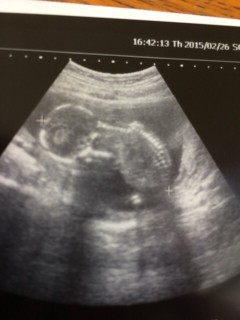

今日は戌の日と検診日。 旦那も一緒に。 赤ちゃんは順調みたいです。 性別はあっさりまだ分かんないよ~といわれガッカリ、、 次回まで持ち越しです。